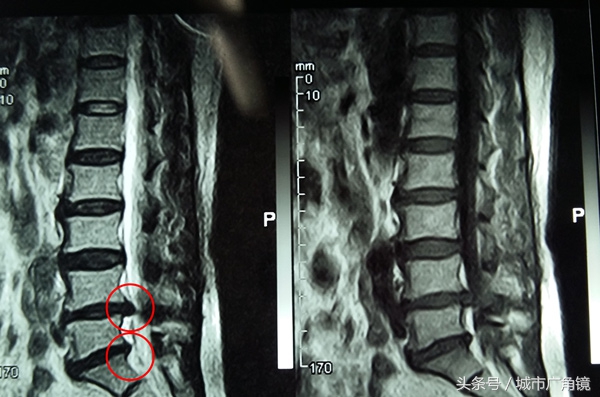

3天前,马大娘经村民介绍,来到医院求诊。经完善化检查后,她被诊断为腰椎间盘突出症。针对具体病情,脊柱科主任张鑫介绍,患者共有两个节段的椎间盘同时突出,也即腰4-5、腰5骶1,神经压迫严重。

在治疗方案上,医生坦言,一方面是实事求是地告知患者病情;另一方面是严谨客观地为其介绍微创和手术的治疗特点。最终的决定权则是掌握在患者及家属手里。他表示,根据其实际情况,加之患者和家属要求彻底解决疼痛的欲望比较强烈,所以为其量身定制了“L4-5,L5-s1腰椎钉棒内固定术+Cage植骨术。”